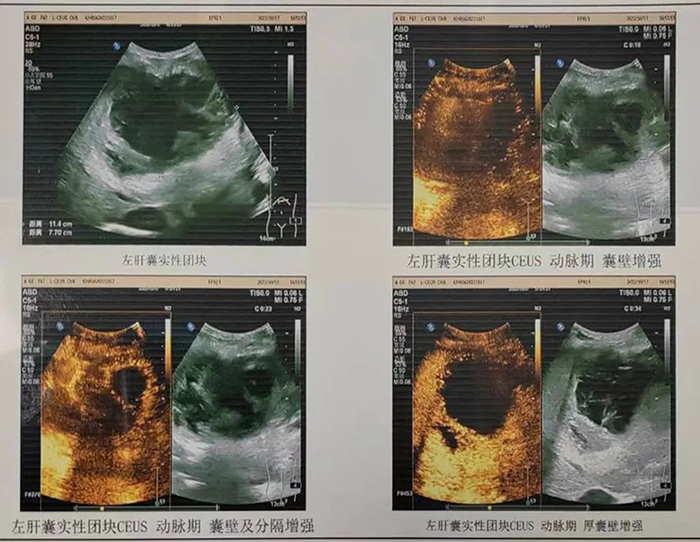

通过耐心做患者家属工作,认真细致地交待手术情况以及各项注意事项,患者家属签署了手术知情同意书。同时,术前为患者再次进行了超声造影检查,确认为典型肝脓肿表现。经过充分评估适应症和禁忌症,超声科副主任赵仲举医生,黄军医生、黄建成医生共同为患者实施超声引导下肝脓肿置管引流。